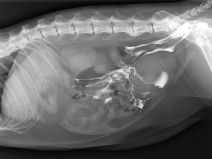

• VETOALP 2025 - Journées du 10 au 13 mars2025 : "Les défis de la prise en charge de l’animal polytraumatisé : de l’urgence à la chirurgie"

Rejoignez-nous à Chamonix du 9 au 13 mars 2025, pour cette nouvelle édition de VETOALP consacrée aux défis de la prise en charge de l’animal polytraumatisé, de son admission en urgence à la chirurgie !

Pour cette édition, l’AFVAC Rhône-Alpes accueille le Groupe d’Étude d’Urgence et Réanimation (GEUR) et le Groupe d’Étude de Chirurgie (GEC), afin d’établir un dialogue au sommet.

Du 10 au 13 mars 2025

Chamonix-Mont-Blanc (74400)

Chirurgie

Traumatologie

Urgence et Réanimation

Rhône-Alpes, G.E.C., G.E.U.R.